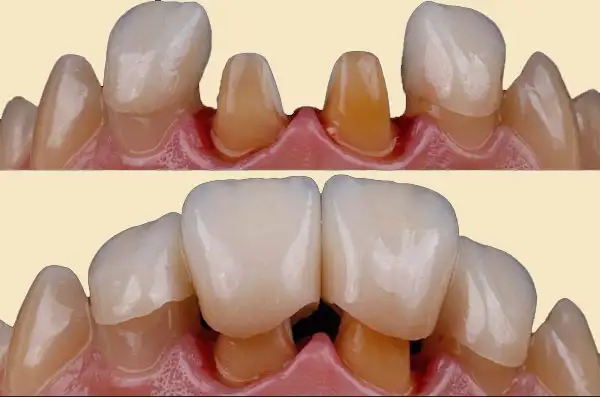

8. Cosmetic Dentistry

Enhances the appearance of your smile using:

• Smile designing

• Veneers

• Tooth reshaping

• Gap correction

Improves tooth shape, color, alignment, and overall smile harmony. Perfect for confidence and aesthetics.